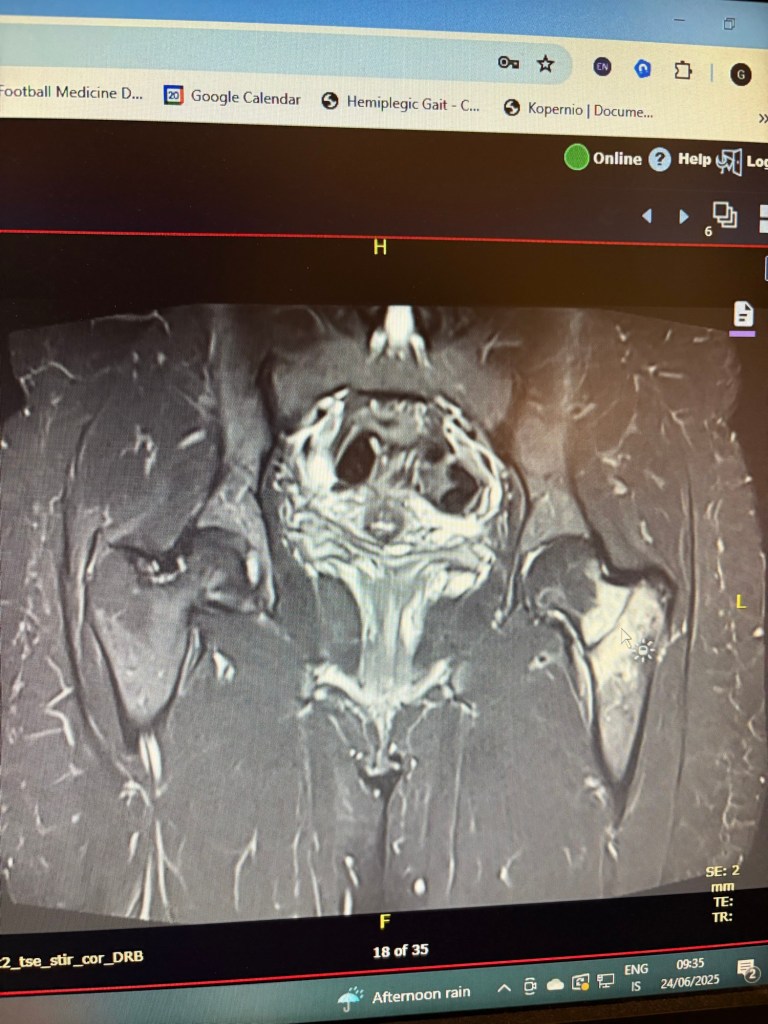

Á mánudegi 23. júní var næstsíðasti tíminn í togmeðferðinni en þá um kvöldið átti ég einmitt tíma í segulómun sem ég hafði grenjað út þegar ég var sem verst. Sjúkraþjálfarinn sagði í djóki að hann væri alveg viss um að ekkert kæmi út úr þessu en ég skyldi nú samt taka tímann fyrst ég hefði fengið hann.

Daginn eftir, á þriðjudeginum, áttum við Þórdís að fara í siglinu með National Geographic. Báturinn átti að fara seinnipartinn; ég fór í togið þennan þriðjudagsmorgun og ég ætlaði svo að vinna til hádegis. Ég kastaði kveðju á Gulla sjúkró á leiðinni út, en þá bað hann mig að bíða aðeins. Sagðist ætla að sýna mér dálítið merkilegt.

Þetta merkilega reyndist vera niðurstaðan úr segulómuninni. Það kom semsagt í ljós á myndunum að lærbeinshálsinn vinstra megin var í sundur. Ég var því búin að vera lærbrotin í sex vikur án þess að vita af því. Það var mikið lán í óláni að brotið hafði ekki aflagast.

Áfallið við að sjá þessa mynd og heyra þessar fregnir var gríðarlegt og ég hugsaði mikið út í allt það sem hefði getað gerst á þessum tíma sem hefði getað aflagað brotið.